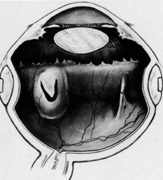

Regardless of which technique or instrument is used for localization and scleral marking, accurate placement of the marks with respect to the intraocular pathology is crucial. For small flap tears or atrophic holes, a single mark on the posterior edge of the break is sufficient. Larger flap tears and nonradial tears require localization of both the anterior and posterior extent of the break (Fig. 6). This anteroposterior orientation is particularly important when radial elements are employed. In areas with multiple, closely spaced tears, it is not necessary to mark each break. Marking the most posterior extent and the circumferential extent of the breaks is adequate (Fig. 7). This approach is also sufficient for marking a retinal dialysis. The circumferential extent of the dialysis is marked anteriorly at the edges of the dialysis, and then the most posterior extent is marked (Fig. 8).

If the retina is bullously detached, accurate localization of retinal breaks is difficult. Bullously elevated breaks appear to lie more posteriorly than their true location because of parallax (Fig. 9). This can result in unnecessarily large and posterior buckles. Inaccurate localization can be minimized by first marking the break at its least elevated margin, usually anterior, and then marking the more elevated margins. Other clues, such as the presence of pigment epithelial changes underlying the break and the location of the ora serrata in relation to the break, may be helpful. Rarely, it may be necessary to drain subretinal fluid to flatten the retina before localization; however, this softens the eye, usually necessitating a saline solution injection to restore volume. It also makes further drainage difficult, presumably because of choroidal swelling secondary to hypotony.

Fig. 9. Apparent posterior location of bullously elevated retinal break caused by parallax.